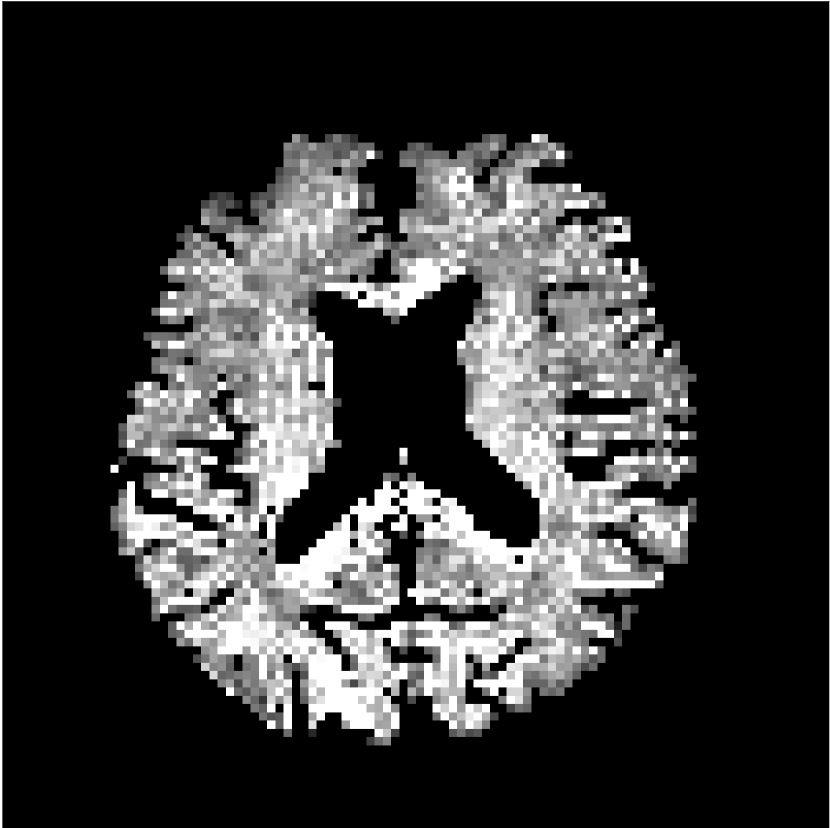

Figure 9 shows parameter maps for the different methods without partial Fourier (No PF) and with 5/8ths partial Fourier (5/8 PF). Mean diffusivities calculated from the raw DWI data (Raw) show notable noise and Gibbs ringing artifacts, while this is substantially removed with the state-of-the-art (SoA) method. However, the state-of-the-art method begins to lose its ability to compensate for the Gibbs ringing and resolution loss when partial Fourier is utilized in the acquisition. The effects of partial Fourier increases are primarily evident in the enlargement of the lateral ventricles and the presence of black lines in the vicinity of the lateral ventricles. The MCNN model is able to compensate somewhat for the ringing effects, but begins to introduce substantial artifacts at the 5/8ths partial Fourier factor, whereas the CCNN model continues to give high-quality mean parameter maps across all PF factors.

Raw

SoA

MCNN

Standard PF

CCNN

b=0𝑏0b=0 s/mm2

No PF

MD, μ𝜇\mum2/ms

5/8 PF

FA

MK

Figure 9: Parameter maps from various methods (with CSF masks for FA and MK). At the top are shown the b=0𝑏0b=0 images from Raw, state-of-the-art (SoA), MCNN, standard partial Fourier, and CCNN methods. Rows 2 and 3 show results for mean diffusivity, rows 4 and 5 show results for fractional anisotropy, and rows 6 and 7 show results for mean kurtosis. The SoA method and both deep learning methods perform well without partial Fourier acceleration; however, at the 5/8ths partial Fourier factor, substantial artifacts are present for all methods other than the CCNN method.

Similar trends are observed in the other diffusion parameter maps.